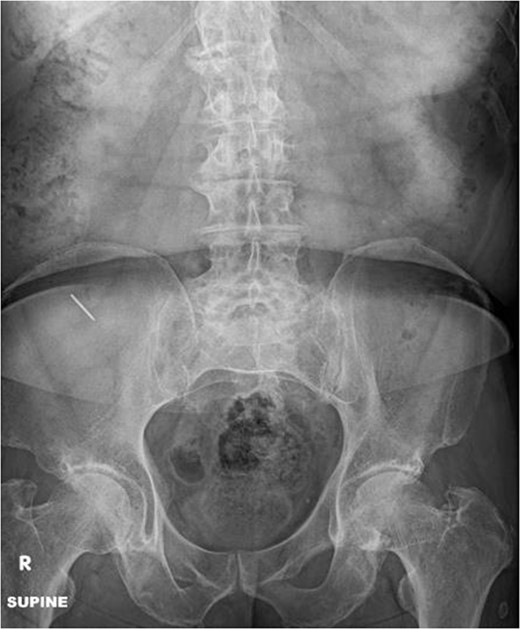

A radiograph of the abdomen was performed which revealed a 2.3 cm linear radiopaque density at the right lower quadrant overlying the right iliac wing (Fig. 1). The gastrointestinal service was consulted and the patient was admitted to the hospital for observation and to undergo colonoscopy the following morning. The patient was started on bowel preparations and otherwise given nothing by mouth.

Abdominal radiograph shows a 2.3 cm linear radiopaque density in the right lower quadrant.